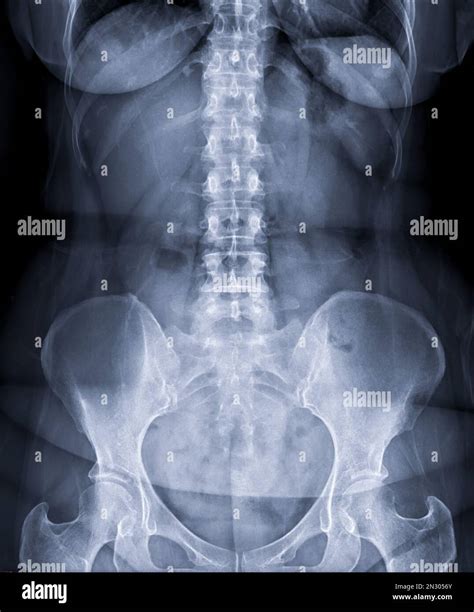

A Lower Back X Ray is a common, non-invasive imaging test that uses a small amount of radiation to create pictures of the lumbar spine. The lumbar spine consists of the five vertebrae in your lower back. By capturing these images, doctors can evaluate the bones, joints, and overall alignment of the lower spine.

Undergoing a Lower Back X Ray is a straightforward and generally quick process. You will be asked to change into a hospital gown to ensure no metal objects, like zippers or jewelry, interfere with the image quality. You may be required to stand, sit, or lie down in different positions—such as on your side or back—so the technician can capture images from multiple angles. This ensures a comprehensive view of the lumbar region.

What Can Be Seen on a Lower Back X Ray?

Scoliosis Abnormal side-to-side curvature of the spine.